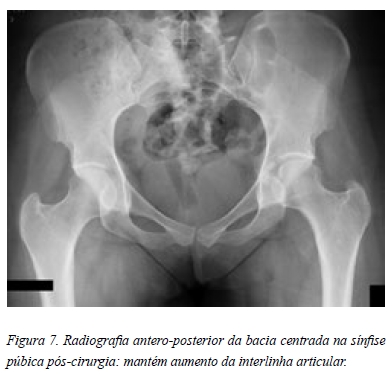

No seguimento pós-operatório observou-se uma melhoria clínica progressiva. O NAHS aos 3 meses era de 73,75 e aos 6 e 12 meses de 87,5. De momento, a paciente não apresenta qualquer recidiva da sintomatologia prévia. De ressalvar a persistência do aumento da interlinha articular (Figura 7).